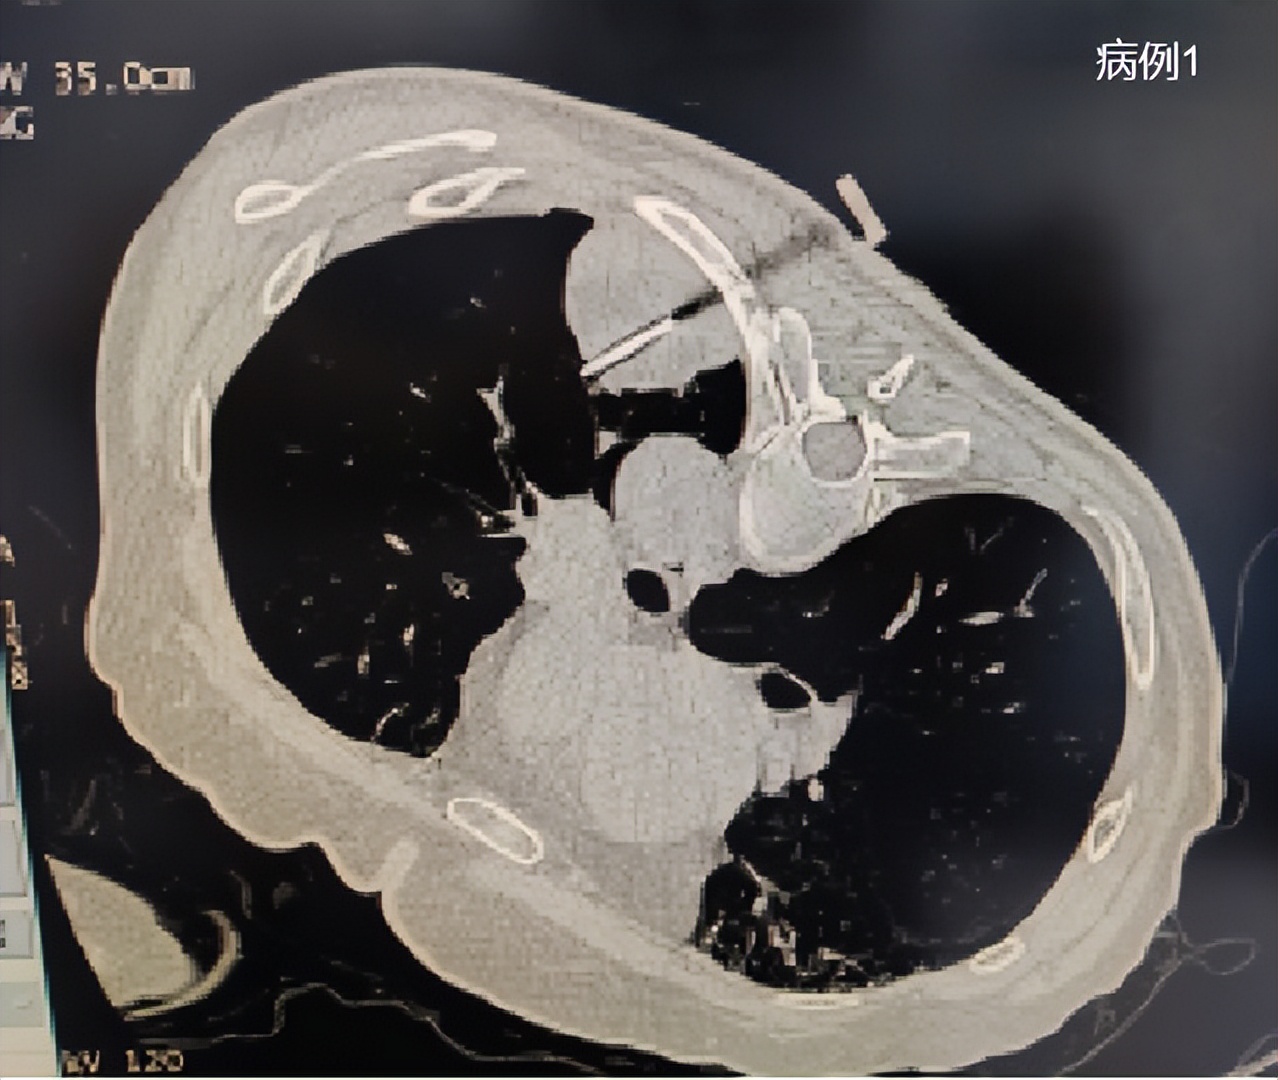

通过CT引导穿刺到结节中心进行冷冻消融

术中需要做三个冷冻消融循环,图中显示为第一个冷冻消融循环形成的冷冻范围